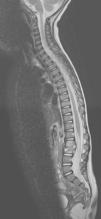

Por la clínica del aparato locomotor, se amplia el estudio y se sospecha una posible afectación de la columna vertebral. La resonancia magnética muestra desestructuración del disco intervertebral L2–L3, con importante afectación de partes blandas que protruyen hacia el interior del canal raquídeo y se introducen a través de los agujeros de conjunción. El estudio electromiográfico revela signos de radiculopatía motora aguda en L2–L3 (fig. 1).

RM de columna completa. El disco intervetebral L2-L3 presenta una marcada alteración de la señal y desestructuración del mismo. Existe un componente de partes blandas posterior que protruye hacia el interior del canal raquídeo, improntando el margen anterior del saco tecal. Discreta rectificación de la cifosis dorsal.